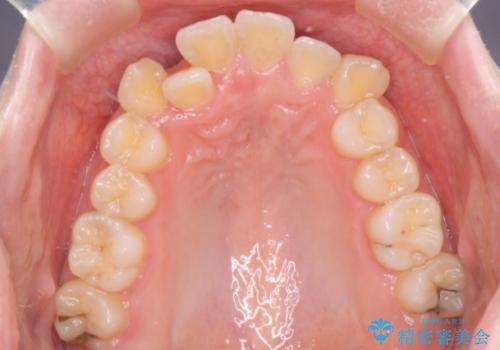

- 患者様は、結婚式までに歯並びを整えたいとのご要望で来院されました。診断の結果、上下左右の第一小臼歯を抜歯し、歯列全体を整える計画としました。審美性を重視し、目立ちにくいホワイトワイヤーを使用した矯正を提案しました。治療期間は2年を目安とし、結婚式までに前歯の整列と噛み合わせを優先的に整えるスケジュールで進めました。定期的な調整と経過観察を通じて、計画的に治療を進めました。

結婚式までに仕上げるため、通常よりも細かく調整を行い、歯の動きを効率的に管理しました。審美ワイヤーを使用したことで、治療中も目立ちにくく、写真撮影などの日常生活での見た目の負担を軽減しました。抜歯部分のスペースを閉じる際には、前歯の位置や噛み合わせのバランスに配慮し、過度な力がかからないよう進めました。患者様の大切なイベントに間に合うよう治療計画を立て、理想的な仕上がりを実現しました。